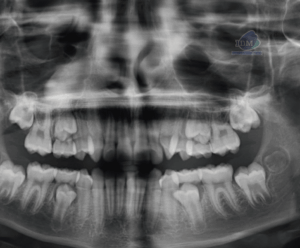

CARACTERISTICAS RADIOGRÁFICAS

La enfermedad de Paget ocurre con más frecuencia en la pelvis, fémur, cráneo y vértebras y en raras ocasiones en los maxilares. Afecta con mayor frecuencia al maxilar superior. Aunque la enfermedad es bilateral puede existir un solo maxilar afectado. La estructura interna se puede observar en tres estadios, el primero radiolúcido, un segundo estadio granular y el tercero se observa como un estadio aposicional tardío más denso y radiopaco. Las trabéculas suelen estar alteradas en cuanto al número y la forma. La densidad media de los maxilares puede disminuir o aumentar dependiendo del número de trabéculas.

Fig 2. Vista posteroanterior del cráneo, revelan opacificación del antro maxilar, radiopacidades de forma irregular que involucran todo el cráneo, Dando una apariencia de copos algodón.